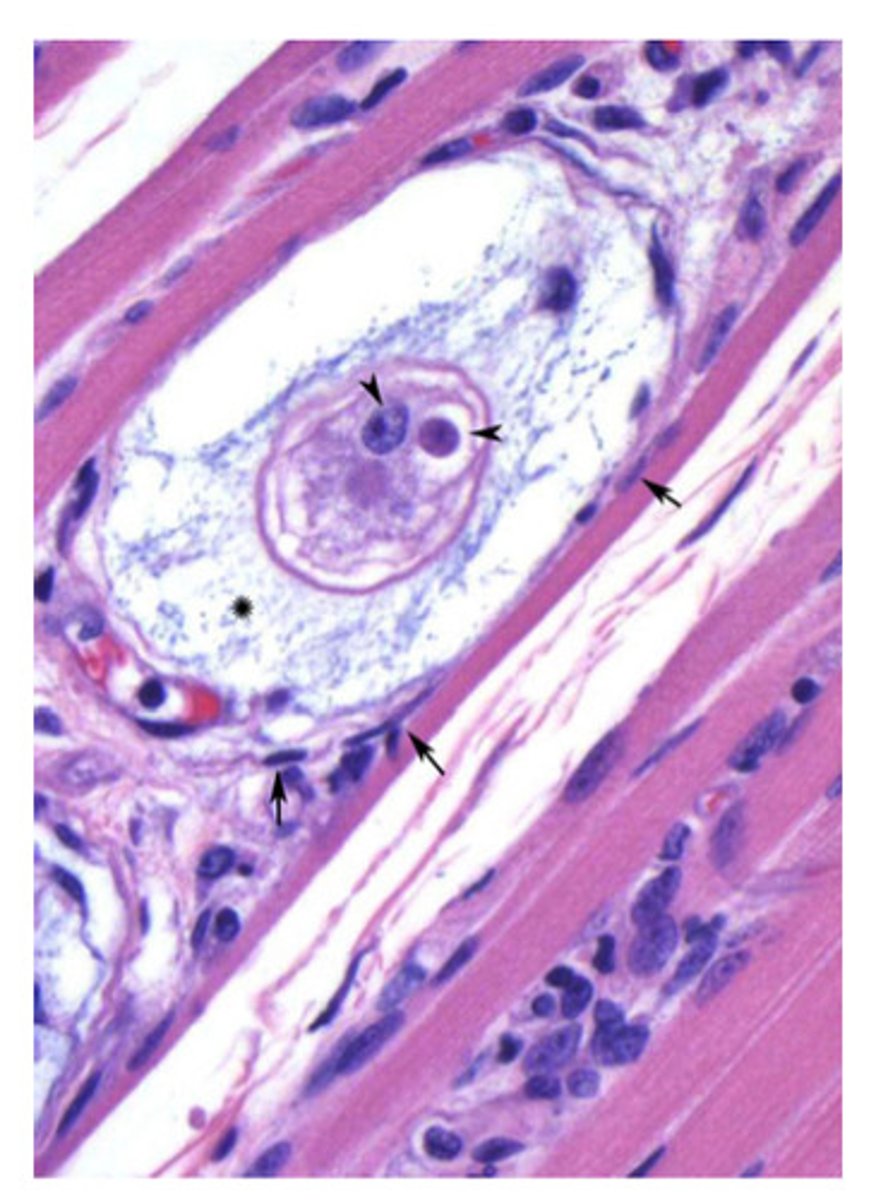

Hepatozoon americanum

ID the following parasite encysted in muscle (dog)